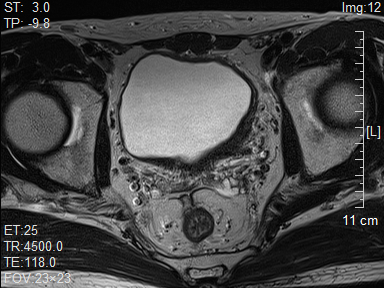

泌尿外科主任薛学义教授带领团队对曾先生的情况进行了全面的评估并仔细阅读影像资料后,考虑其为T2期膀胱癌。

▲治疗前肿瘤情况

针对曾先生的需求,薛学义教授团队经过多学科讨论,决定尝试为他制定个体化治疗方案——保留膀胱综合治疗,即尽量保留患者正常膀胱功能的前提下,通过手术、放疗、化疗等多种方式联合治疗肿瘤,尽可能减少不良反应,达到控制疾病和提高生活质量的目的。